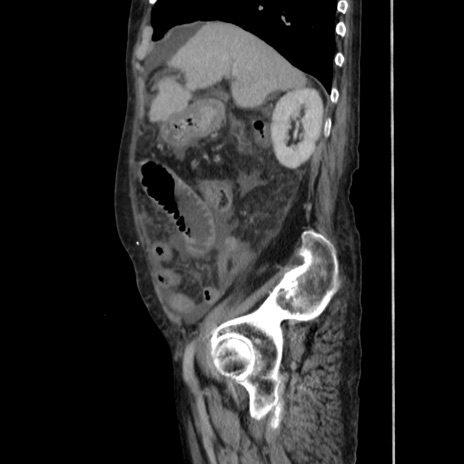

症例31(矢状断像)

【症例】80歳代 女性

【主訴】腹部膨満感

【現病歴】他院にて肝硬変にてフォロー中。1週間前から便秘、腹部膨満感、臍部腫瘤あり受診となる。

【既往歴】肝硬変

【身体所見】腹部膨隆あり、皮膚変化なし、疼痛なし。

【データ】WBC 4600、CRP 0.25